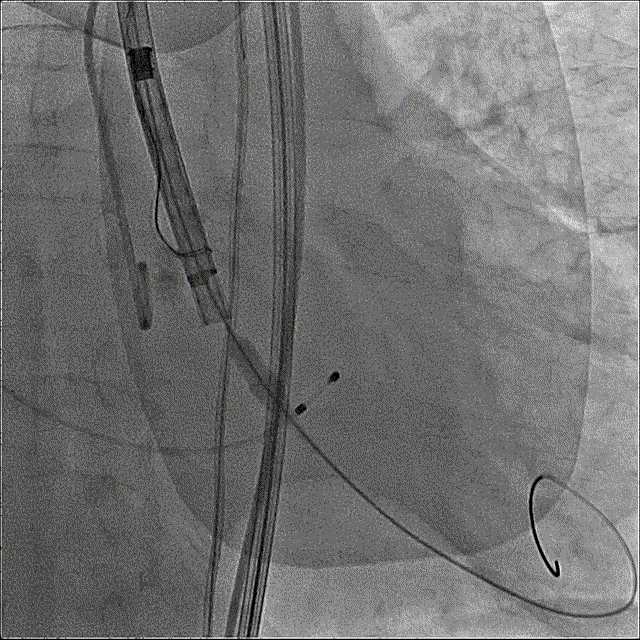

最终造影

主动脉弓剪影,瓣膜植入深度3mm,冠脉显影正常,主动脉弓正常

术后即刻情况